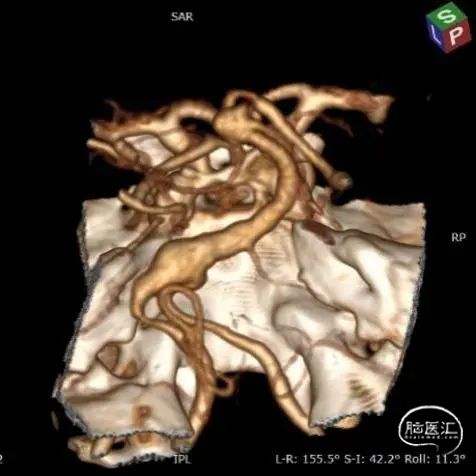

图3. 双侧颈总动脉造影:A和B为右侧颈总动脉造影提示颈内动脉颅内段迂曲,后交通动脉开放;C和D为左侧颈总动脉造影也可见颈内动脉迂曲,后交通动脉开放供应同侧大脑后动脉。